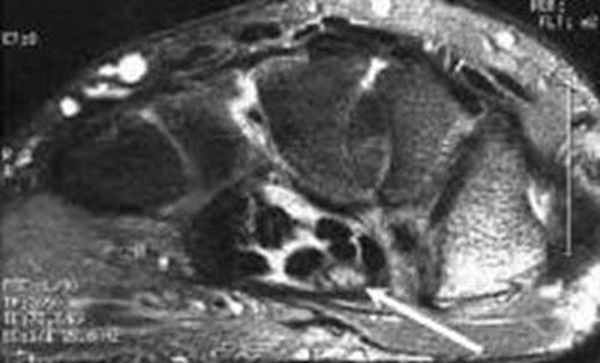

Перелом ладьевидной кости с явлениями асептического некроза проксимального полюса и, связанного с ним, остеоартрита. Ладьевидный перелом обычно происходит из-за падения на вытянутую руку, которое приводит к гиперэкстензии лучезапястного сустава.

Аваскулярный (асептический) некроз нередко сопутствует переломам проксимальной части ладьевидной и переломам полулунной кости, а также неадекватно репонированным и иммобилизированным переломам этих костей. Основная причина – нарушение трофики участка кости при повреждении питающих артерий.

Методом выбора в диагностике и стадировании остеонекроза костей кисти является МРТ.